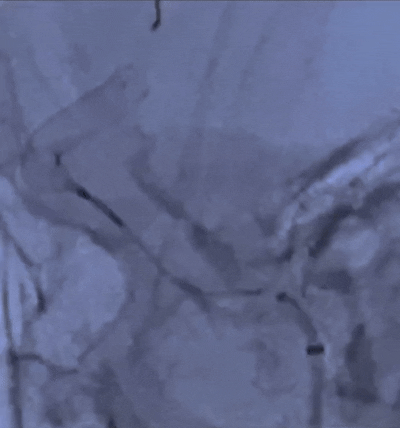

导丝按摩,令近远端和弯曲血管更贴壁。

术后造影可见动脉瘤囊内造影剂即刻滞留,通桥麒麟™血流导向密网支架尾端完全打开,贴壁良好,支架内血流畅通。